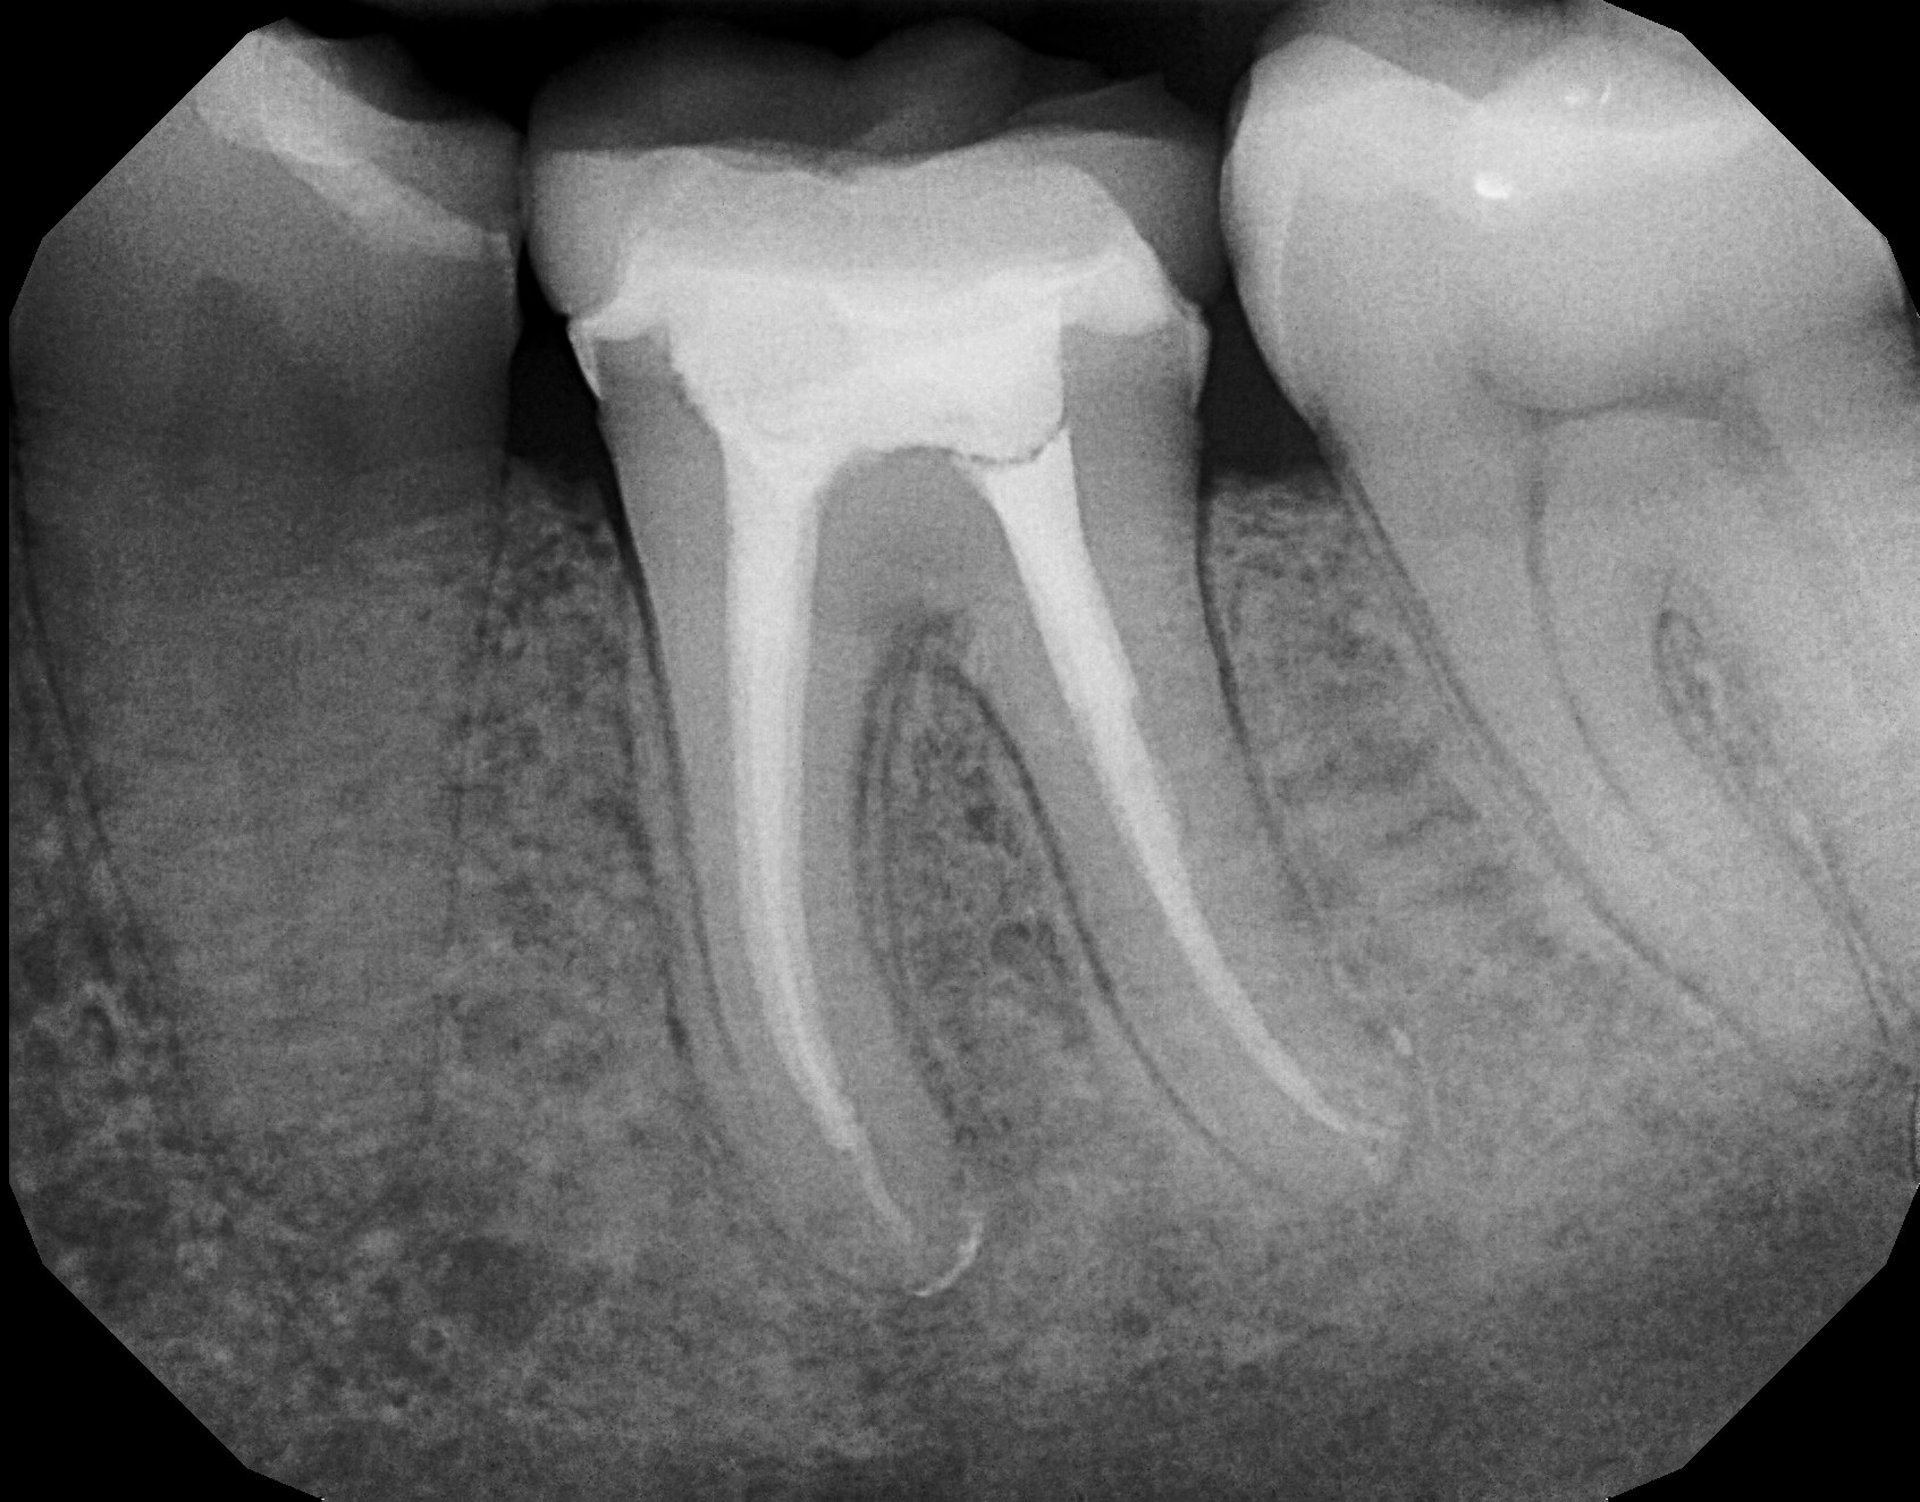

A root canal is a dental procedure that removes the infected or inflamed pulp from inside a tooth. The pulp contains nerves and blood vessels, and when it becomes compromised due to deep decay, trauma, or cracks, it can cause intense pain and swelling. During treatment, the canals are cleaned, disinfected, and sealed to prevent reinfection.

Diagnosis & Imaging: We use digital X-rays to assess the extent of infection.

Pulp Removal & Cleaning: The infected tissue is removed and canals are disinfected.

Sealing & Restoration: The tooth is sealed and often restored with a crown for durability.